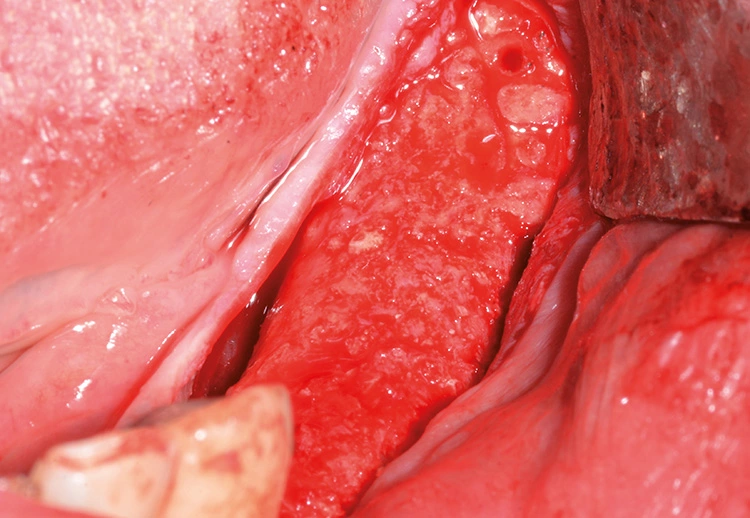

Implantation: 7 Monate nach Augmentation

Tröltzsch

Tröltzsch Tröltzsch

Tröltzsch Tröltzsch

Tröltzsch Tröltzsch

Tröltzsch Tröltzsch

Tröltzsch Tröltzsch

Tröltzsch Tröltzsch

Tröltzsch Tröltzsch

Tröltzsch Tröltzsch

Tröltzsch

Trotz der schlechten, hart- und weichgewebigen Grundvoraussetzungen konnte der Kieferkamm zufriedenstellend rekonstruiert werden. Die Augmentation des kombinierten, horizontalen und vertikalen Defekts mit Yxoss CBR®, Geistlich Bio-Oss®, Geistlich Bio-Gide®, autologem Knochen und PRF ermöglichte die Implantation mit hoher Primärstabilität in den rekonstruierten Bereich.